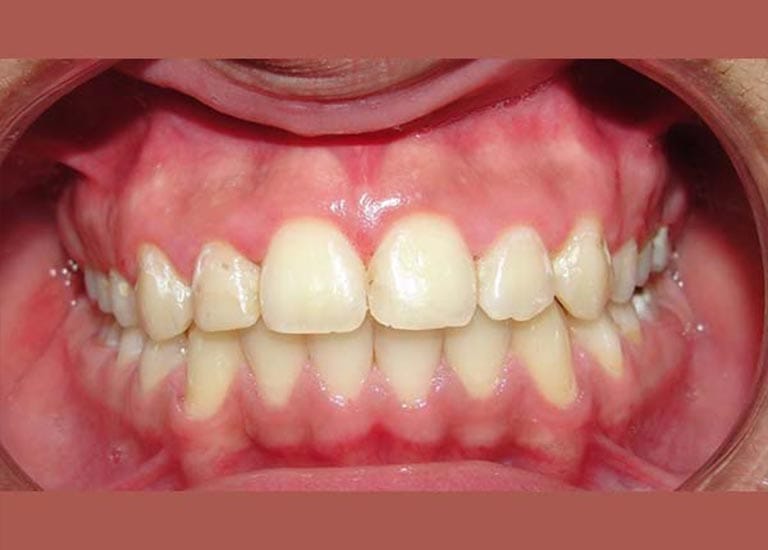

AFTER

So we decided to extract these two molars and use their space to return the front teeth back, in the end, our friend regained his beautiful smile again.